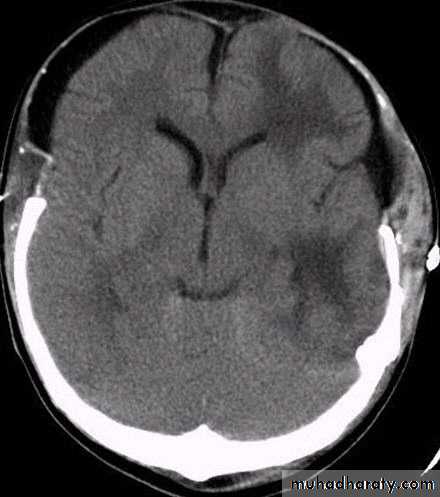

Chronic Subdural Haematoma

CT scan: the acute clotted blood is initially appears white (hyperdence), but as it liquefies, it slowly becomes black (hypodense).

They should be drained if they continue to enlarge.

They are evacuated by drilling burrholes over the collection and washing it out with warmed saline.